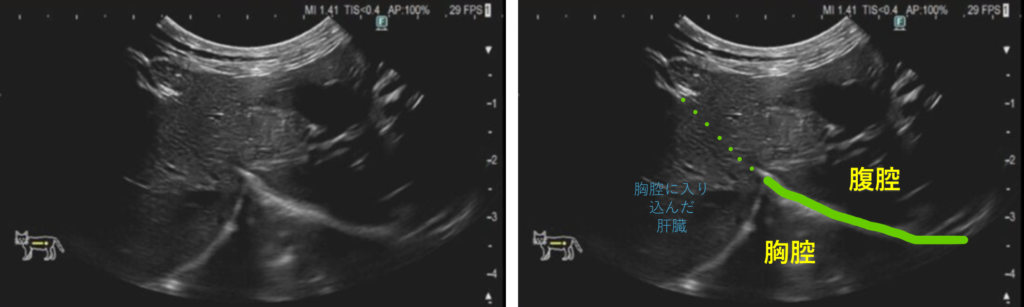

PPDHの診断には、胸部X線検査や超音波検査が有効であり、心膜腔内に腹部臓器が見られることで診断がつきます。場合によってはCT検査やMRIなどの高度画像診断も用いられ、他の胸腔内疾患との鑑別に役立ちます。

症例は、 スコティッシュフォールド、7か月齢、未避妊の女の子です。ヘルニアの整復を行うにあたり、避妊手術も同時に行いました。